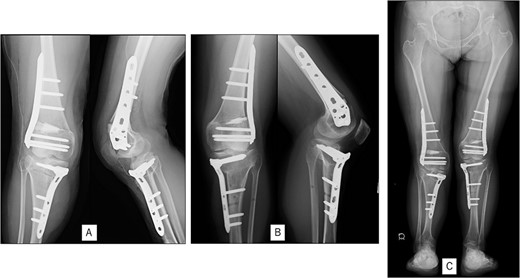

A 23-year-old woman presented with bilateral knee pain and gait abnormalities owing to marked lower extremity deformity. She was diagnosed with EVC as a child but had never been followed up by orthopedics because she was not in pain. On physical examination, marked valgus instability was observed in both knees, and the motion of both knees ranged from 10° to 135°. Radiographic examinations of both knees, including computed tomography, showed valgus deformity, lateral and anterior depression of the proximal lateral tibial plateau, and external rotation deformity of the lower leg. Patellar dislocation was observed in the right knee (Fig. 1). The radiological angles are presented in Table 1. The right knee underwent surgery first, followed by the left 10 months later. Lateral and medial skin incisions were made. Extensive lateral retinacular release, fractional lengthening of the distal lateral hamstring, and Z-lengthening of the iliotibial band were then performed. At this stage, peroneal nerve strain was identified, and decompression of the peroneal nerve was performed. Osteotomy was subsequently performed on the tibia. Closed-wedge varus and derotational osteotomy of the proximal tibia and open-wedge varus osteotomy of the distal femoral varus were performed. In addition, vastus medialis advancement was performed on the right knee, and patellar realignment was achieved in extension (Fig. 2). However, the knee showed a subluxation tendency owing to flexion of >30°; therefore, the postoperative rehabilitation plan progressed more slowly than that of the left knee. Range of motion training began on the left knee immediately after surgery without any restrictions, but on the right knee only after 3 weeks of postoperative immobilization in the extended position. However, ambulation exercise was performed on both knees with no loading for 3 weeks, then partial loading was initiated, and full loading was permitted at 8 weeks postoperatively. Early postoperative standing radiography showed residual mild valgus deformity of the lower limbs (Fig. 2, Table 2). In addition, the right knee showed patellar re-dislocation 2 months postoperatively, and the patellar deformity gradually progressed owing to the femoral implant; therefore, the patient underwent implant removal, tibial tubercle transfer, and medial patellofemoral ligament reconstruction 1.5 years after the initial surgery (Fig. 3). Six months later, she fell while walking and developed a fracture at the osteotomy of the right femur; open reduction and internal fixation were performed (Fig. 4). The remaining years passed uneventfully, and 10 years after the initial surgery, the patient still had mild valgus deformity of the lower limbs, but had no recurrence other than that experienced immediately after surgery, no complaints of knee pain, and a stable gait (Fig. 5, Table 2).

Radiography after right patellar re-dislocation and repair surgery: (A) the patella is eroded owing to contact with the femoral plate. (B) Skyline view after patellar repair surgery. (C) Anteroposterior and lateral view after patellar repair surgery.